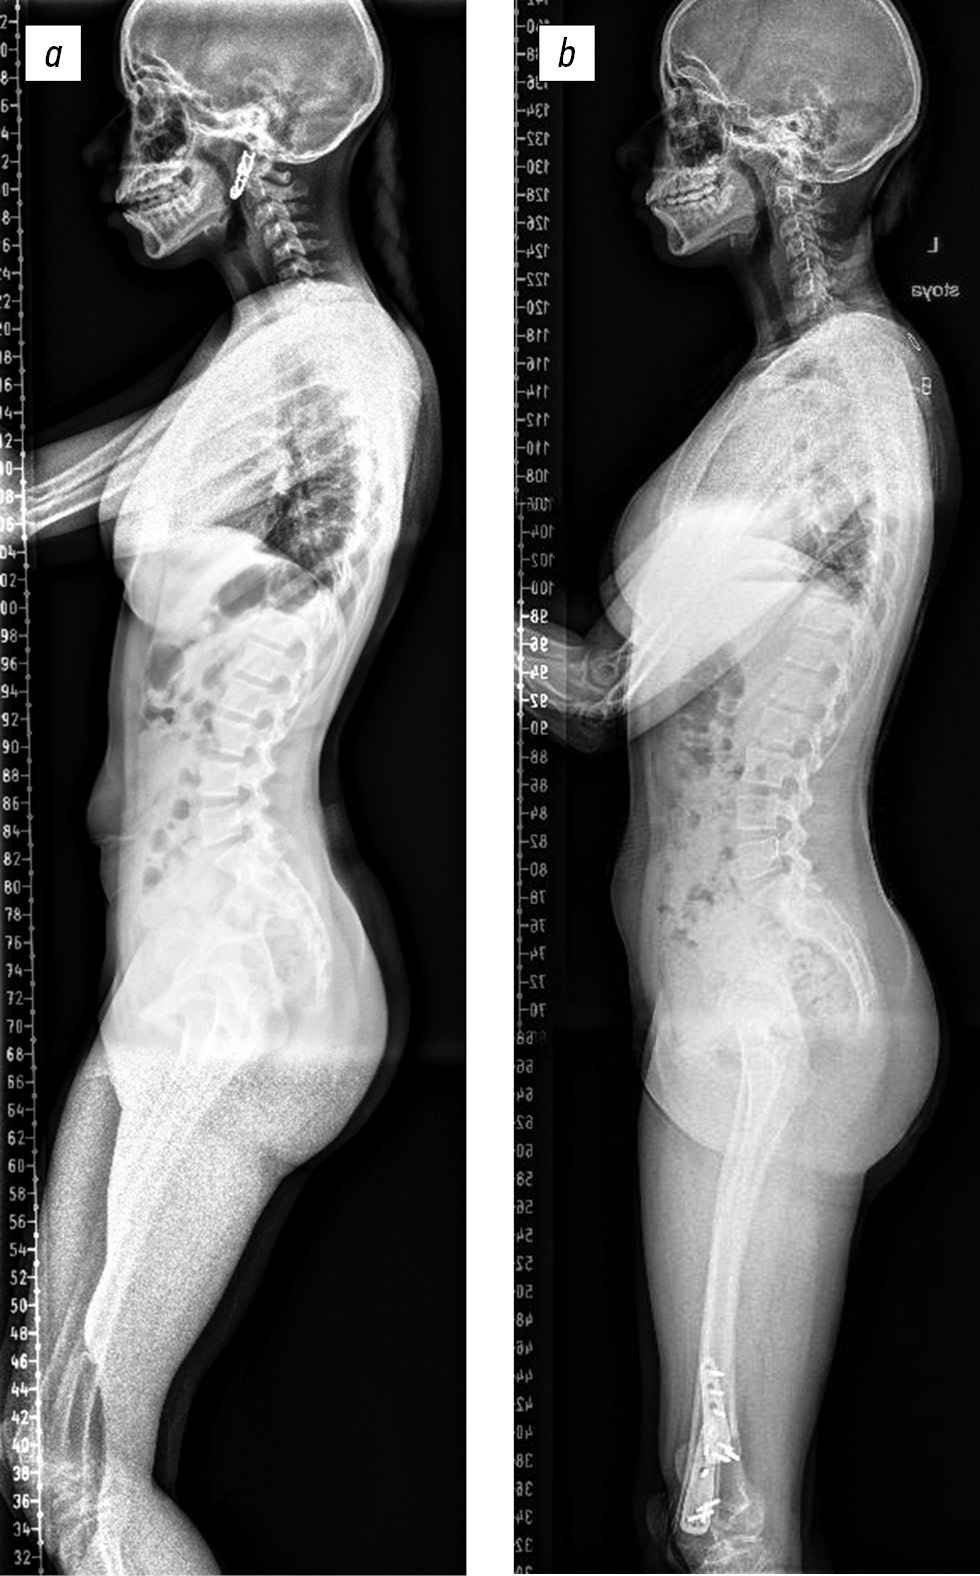

Хирургическое вмешательство во всех наблюдениях позволило устранить СККС (рис. 3).

Рис. 3. Общий вид пациента сбоку: a — до хирургического лечения; b — после хирургического лечения.

Рис. 5. Рентгенограммы скелета в боковой проекции: а — до хирургического лечения; b — после хирургического лечения.